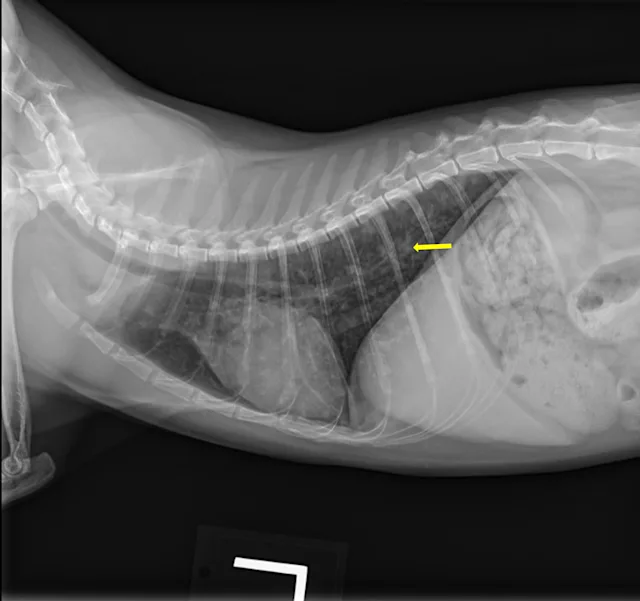

At the 2-month recheck, continued clinical improvement was observed. The owner reported Eleanor was doing well at home. Her body weight had increased to 8.3 lb (3.8 kg); BCS was 4/9.On physical examination, mildly increased bronchovesicular sounds were still present. Fundic examination results were normal. Thoracic radiographs showed continued improvement; remaining lesions were predominantly in the peripheral lung field with a more caudodorsal distribution (Figure 3).

A

FIGURE 3 Left lateral (A), right lateral (B), and ventrodorsal (C) thoracic radiographs 2 months after initiation of itraconazole. Remaining lesions (arrows) were predominantly in the peripheral lung field with a more caudodorsal distribution.